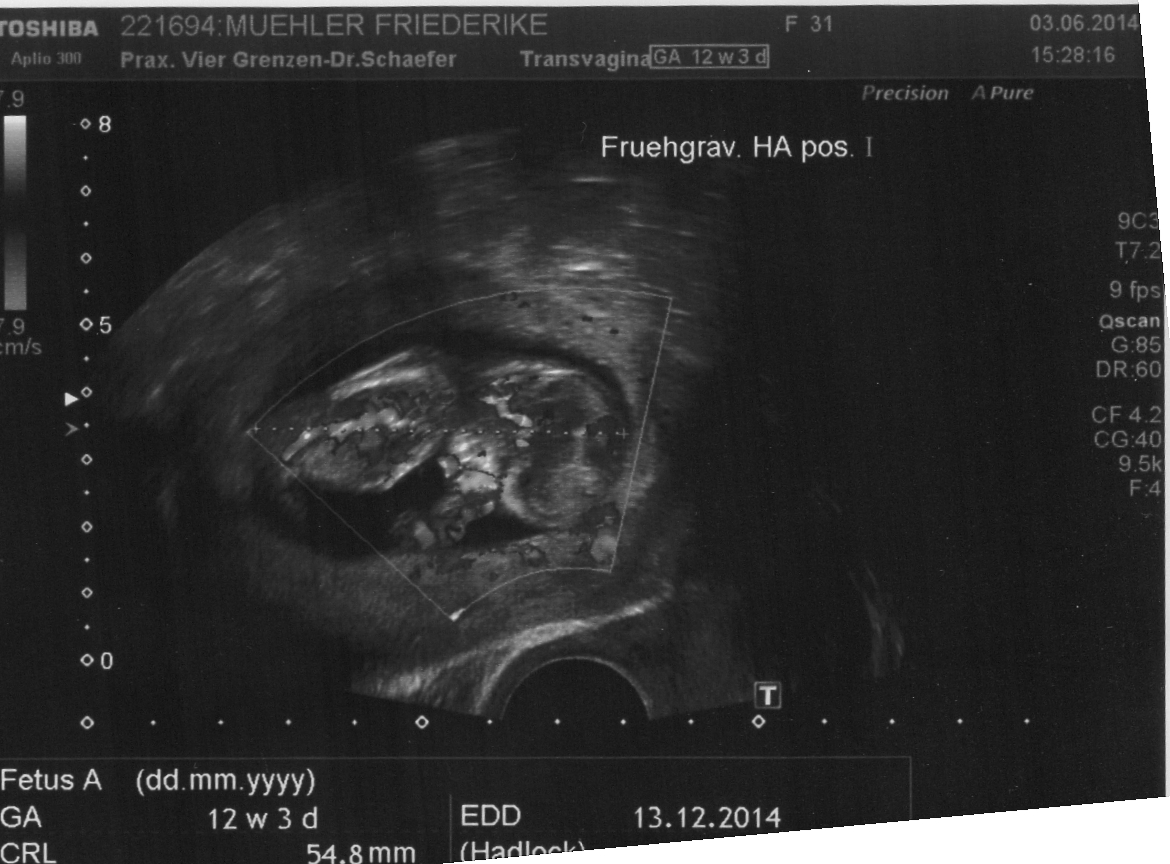

Heute gab es ein Fotoshooting der besonderen Art beim Opa auf Arbeit. Sein Kollege, der stellvertretende Chefarzt der Kinderklinik und gleichzeitig Guru des Ultraschalls, hatte sich bereit erklärt den werdenden Eltern noch ein paar aktuelle Fotos zu machen. Leider gab es kein 3D, aber dafür ein paar süße Fotos und vor allem Videos unseres Sohnemannes, der sich die ganze Zeit über ruhig verhielt und sich der Kamera, äh dem Schallkopf stellte.